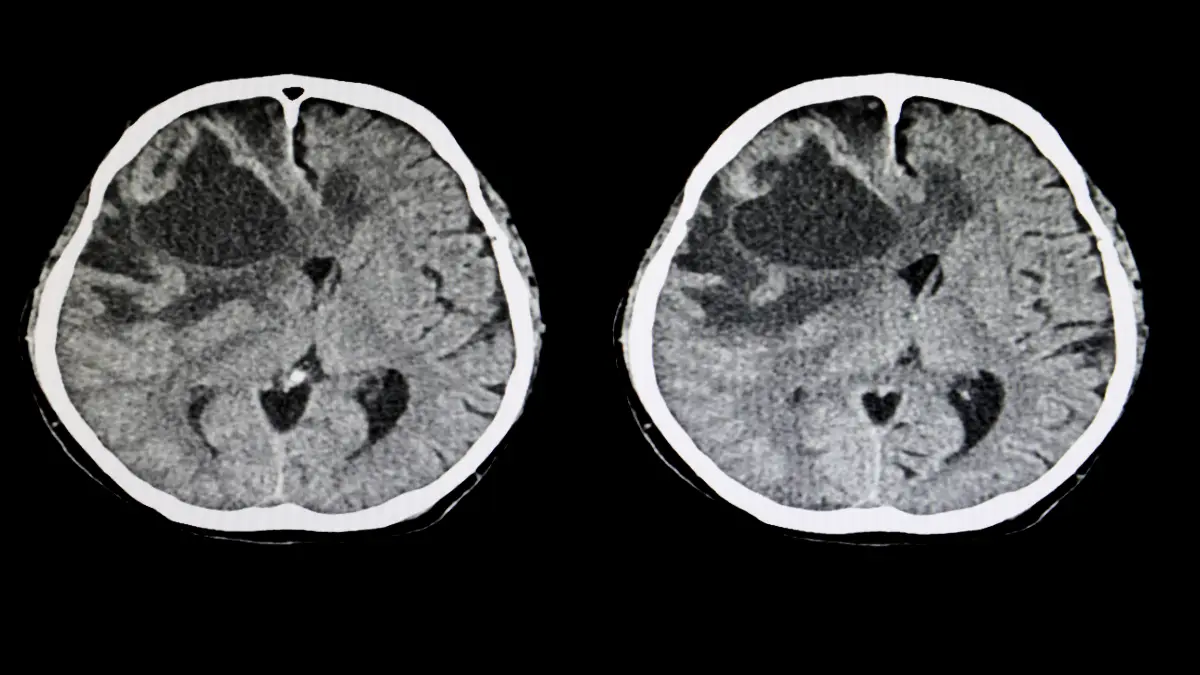

Differenziertes Vorgehen für Anfälle bei Autoimmunenzephalitis